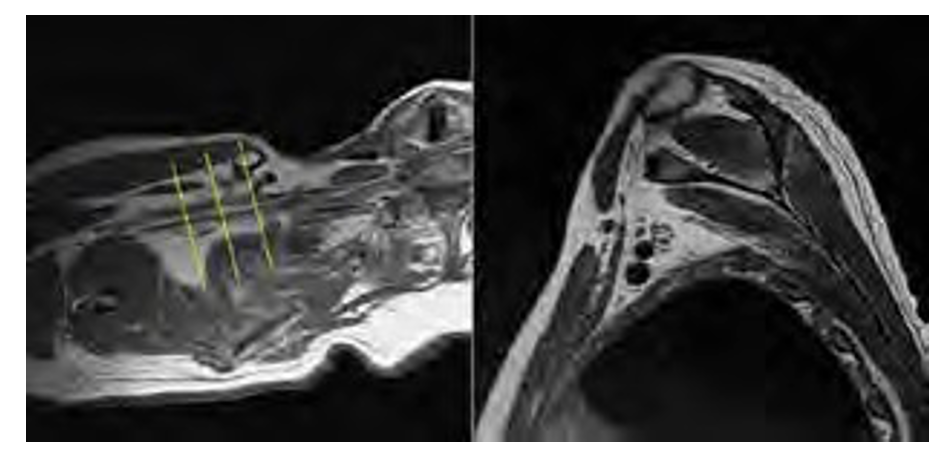

AXIAL

CORONAL